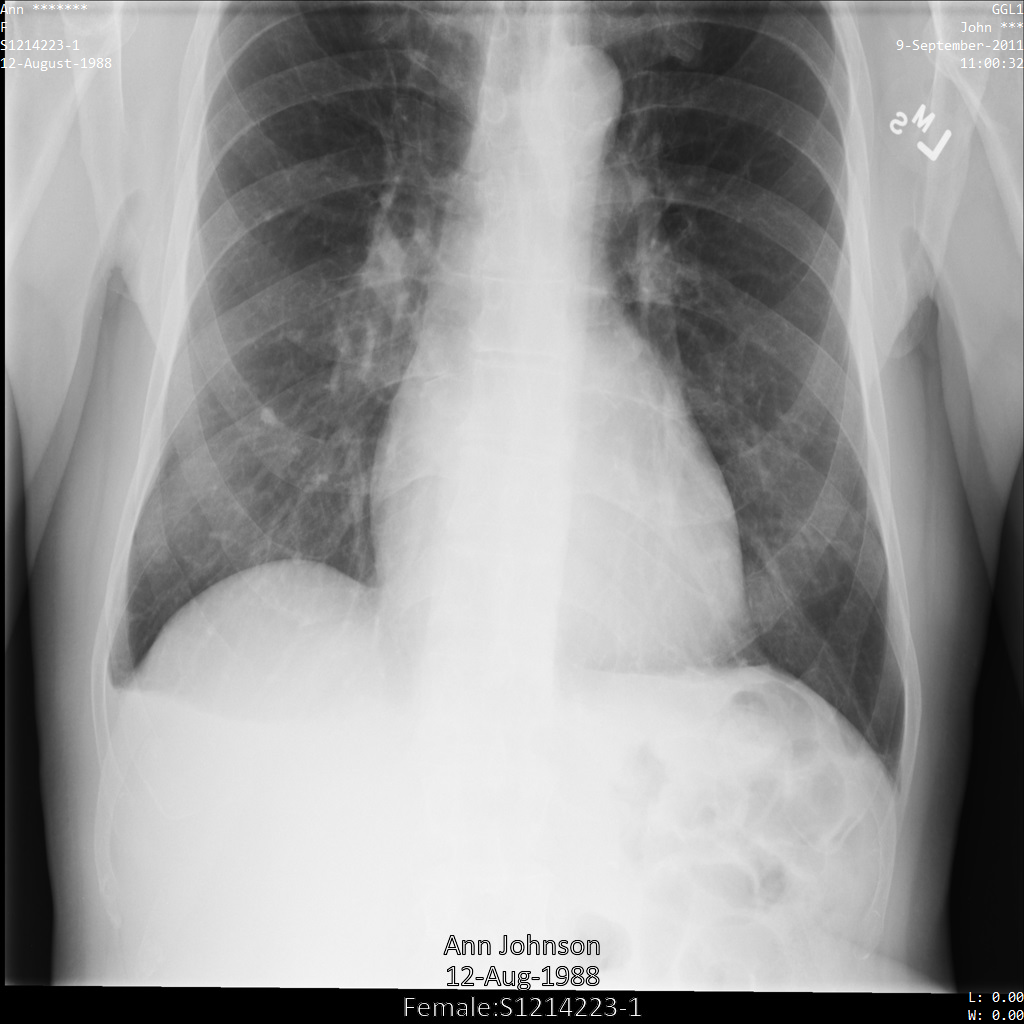

Setiap bagian berikut memberikan contoh cara melakukan de-identifikasi data DICOM menggunakan berbagai metode. Output gambar yang tidak diidentifikasi disediakan dengan setiap sampel. Setiap sampel menggunakan gambar asli berikut sebagai input:

Anda dapat membandingkan gambar output dari setiap operasi penghapusan identitas dengan gambar asli ini untuk melihat efek operasi.

Setelah mengirimkan gambar ke Cloud Healthcare API, gambar akan muncul seperti berikut. Meskipun metadata yang ditampilkan di sudut atas gambar telah disamarkan, informasi kesehatan terlindungi (PHI) yang tercetak di bagian bawah gambar tetap ada. Untuk juga menghapus teks sisipan, lihat Menyamarkan teks sisipan dari gambar.